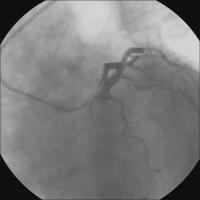

Sondierung - BMW-Führungsdraht

Abbildung 3: Sondierung beider Ästen mit je einem BMW-Führungsdraht (Guidant). Vordilatation des Ramus diagonalis mit einem 2,5 / 20 mm-Ballon (Hypro Pegaso, Sorin Biomedica) - 16 atm.

Keywords: KardiologieKoronarangiographieRamus diagonalis